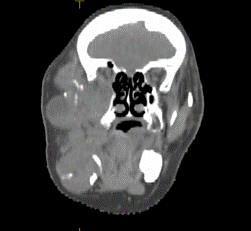

A cervicofacial contrast CT scan of the mandible revealed a tumor process involving the right hemiface (Figure 2), responsible for horizontal and vertical branch lysis as well as temporomandibular joint and lysis of the external edge of the right maxillary sinus (Figure 3), with retro-orbital extension measuring 12x8x6,5 cm compatible with tumor recurrence. Although biopsy shows ameloblastoma with follicular type.

Figure 2. CT showing swelling in the right mandibular region deforming the right hemiface

Figure 3. CT showing the tumor process leading to lysis of the external edge of the right maxillary sinus